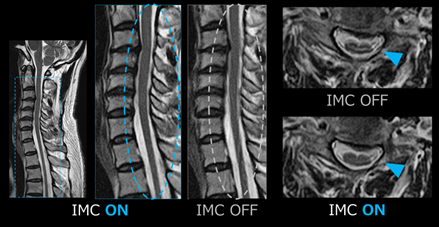

体動アーチファクトは救急患者のように意思疎通が困難な場合や生理的な動きが原因の場合に対応が難しく、検査で苦慮することが多くあります。 Gracianにはラジアルサンプリング法「JET」に加えて、「IMC」が搭載されています。IMCはカーティシアン法の体動補正機能で、 ラジアルサンプリング法に比べコントラスト変化が少なく、撮像時間の延長も抑えられるため、検査に組み込みやすいです(Fig.7)。 キヤノンMRIは頸部や椎体など画質差が出やすい部位でも画質が綺麗で、IMCの効果と相まって、より高画質な画像を得ることができます。

IMC前後の比較画像

Fig.7 IMC前後の比較画像